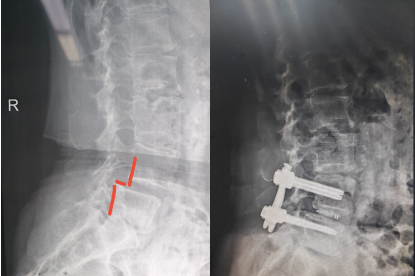

该患者半年前出现腰部及右下肢的疼痛,但休息后尚能缓解最近症状加重,身体出现侧弯,严重影响了日常生活。患者四处求医,但一直因惧怕开放手术的创伤,故一直未选择手术治疗。了解到苏州高新区人民医院一直开展的微创脊柱内镜手术,遂前来就诊,行核磁共振检查后,发现腰4椎体向前明显滑脱,椎间盘突出,椎管狭窄,压迫左侧神经根需要行腰椎滑脱椎间盘切除,椎管减压,滑脱复位,椎间植骨融合内固定手术。医院骨科脊柱微创中心刘勇主任团队为她制定了微创手术方案,腰部创面非常小。

术后患者恢复顺利,术后六天即顺利下地行走,步态正常,原腰疼和下肢疼痛,麻木症状消失,患者对手术效果非常满意。医院脊柱微创中心自2020年成立以来,依托多项微创技术,对脊柱患者尤其腰椎间盘突出症的患者进行微创手术治疗,从单纯的椎间盘突出,椎管狭窄到严重的腰椎滑脱,均可采用微创手术解除患者病痛,为此也树立了良好的口碑。